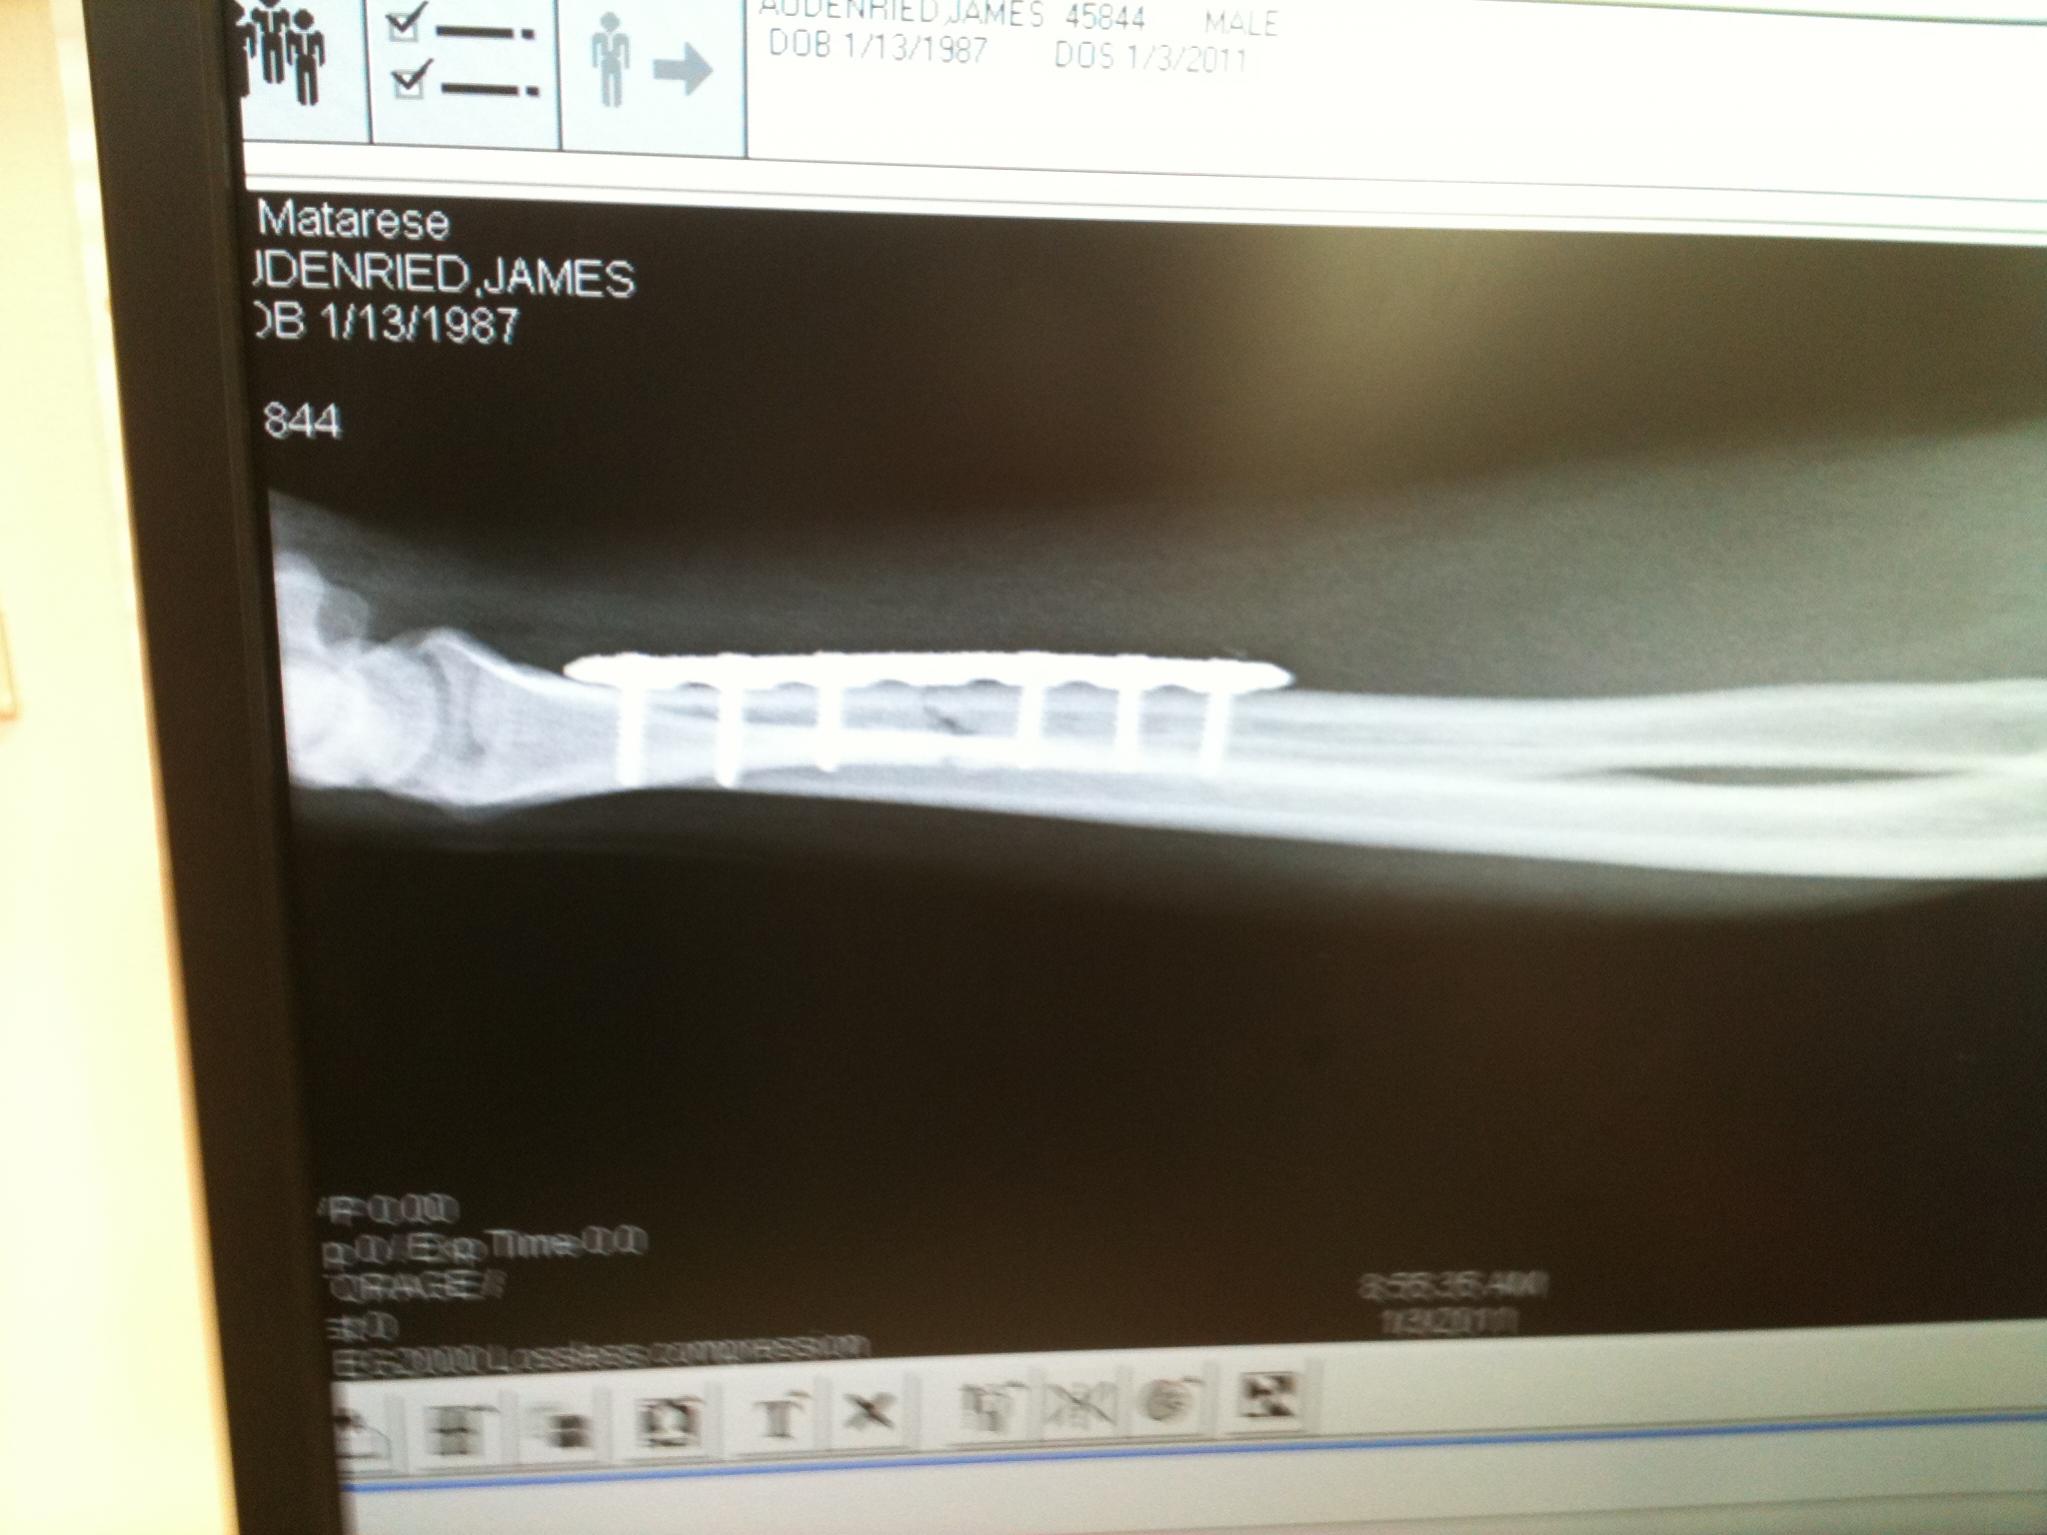

I just put a 50mm tial bov and new charge pipe on, the next day it rained I couldnt drive the car hard. Next day after work I went snowboarding some kid wipes out in front of me, I jumped over him caught an edge, face flopped broke my arm, 2 days later had surgery 5inch plate and 6 screws, in a cast past my elbow, cant drive.